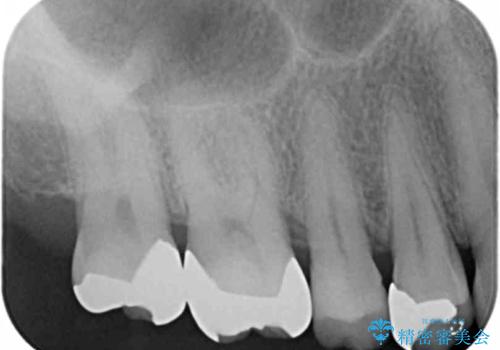

ゴールドは色調がめだつものの上の奥歯はほとんど見えることがないため、色調の問題以上に咬合力が強い場合(ゴールドは破折リスクが低い)や複雑な修復を要する場合(ゴールドは複雑な加工も行いやすく、薄く加工することもできる)に選択をお勧めすることがあります。

今回、噛み合わせが強く、目立たない場所でもあったためゴールドによる修復を行いました。